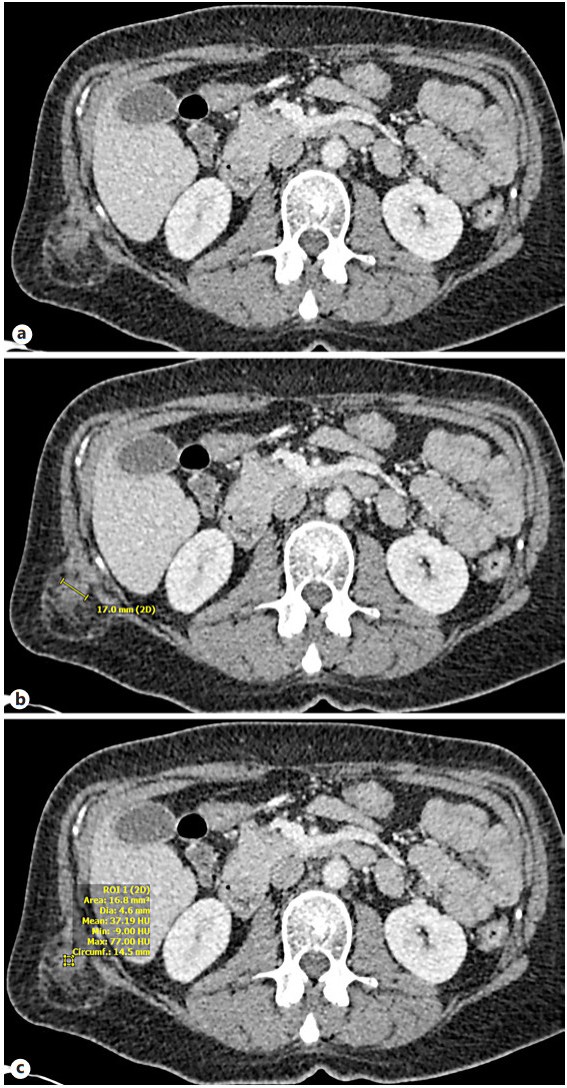

Results: Cryoablation of this mass was successful with no complications. CT images during the procedure demonstrated circumferential coverage of the entire lesion with no injury to the surrounding tissues.